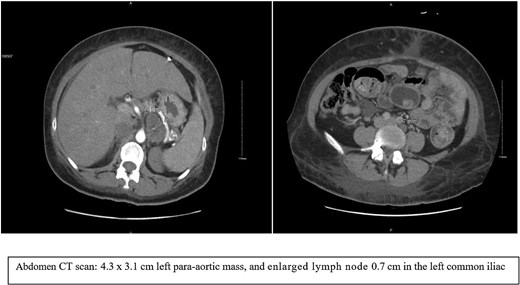

The patient was admitted electively for the planned laparoscopic left adrenalectomy. Intraoperatively, the left adrenal gland was identified and appeared normal. A large para-aortic mass, ~5–6 cm, was found near the adrenal, adherent to it, and attached to the splenic artery. The mass was resected and completely removed. Veins draining into the renal vein were clipped. The final procedure involved resection of the retroperitoneal mass without removal of the adrenal gland, as shown in Fig. 4. The patient tolerated the surgery well and had an uncomplicated postoperative course.

Final histopathology: no intact adrenal gland was found, and a panel of immunostains was performed. Tumor cells are positive for S100 and negative for NFP, SMA, HMB45, MelanA, and Desmin, indicating a neural origin or Schwann cell origin.